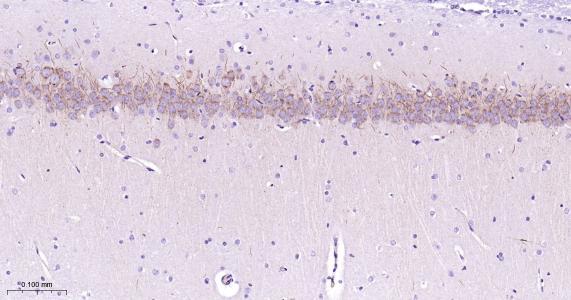

Paraformaldehyde-fixed, paraffin embedded Human Cerebellum; Antigen retrieval by boiling in sodium citrate buffer (pH6.0) for 15 min; Antibody incubation with IP3 receptor Monoclonal Antibody, Unconjugated(bsm-61555R) at 1:200 overnight at 4°C, followed by conjugation to the bs-0295G-HRP and DAB (C-0010) staining.